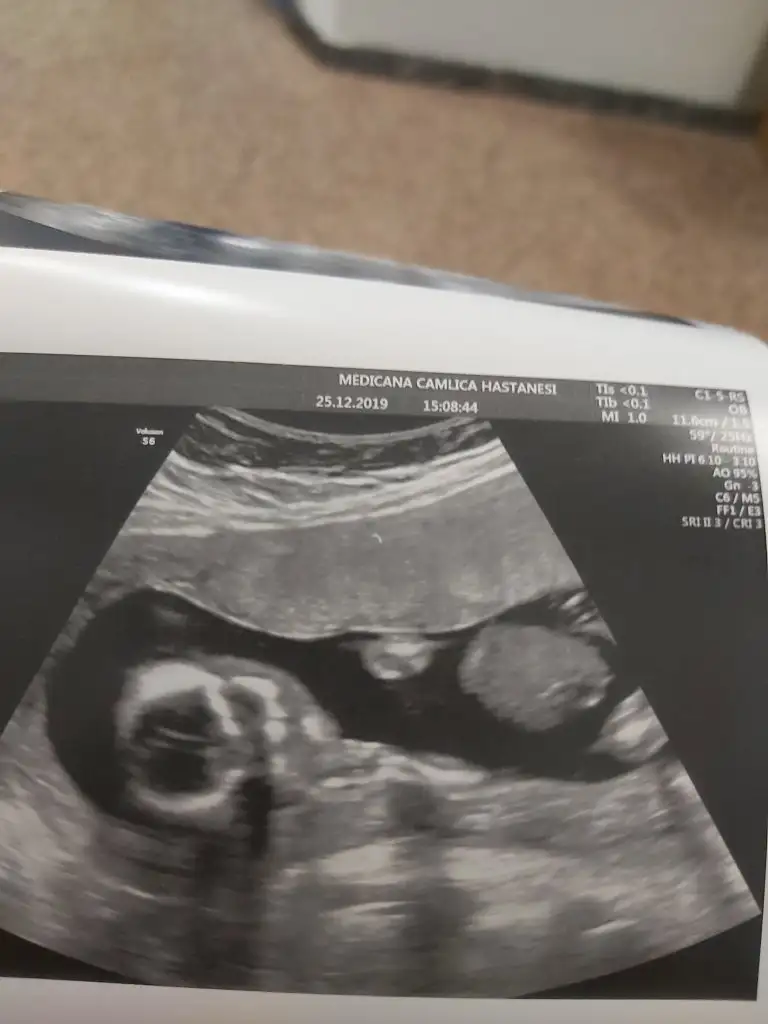

dr soylemeden siz gorun genital nub teorisi ( bebegin cinsiyeti)

Siz de yine bakarmısınız net söyledi kız diye herkes erkek demişti sizin gibi bende öyle diyordum ama ters köşe yaptı galiba bizimki çok hareketliydi 🤭🤣

• 20191225_151603.webp

20191225_151603.webp

24,9 KB · Görüntüleme: 44